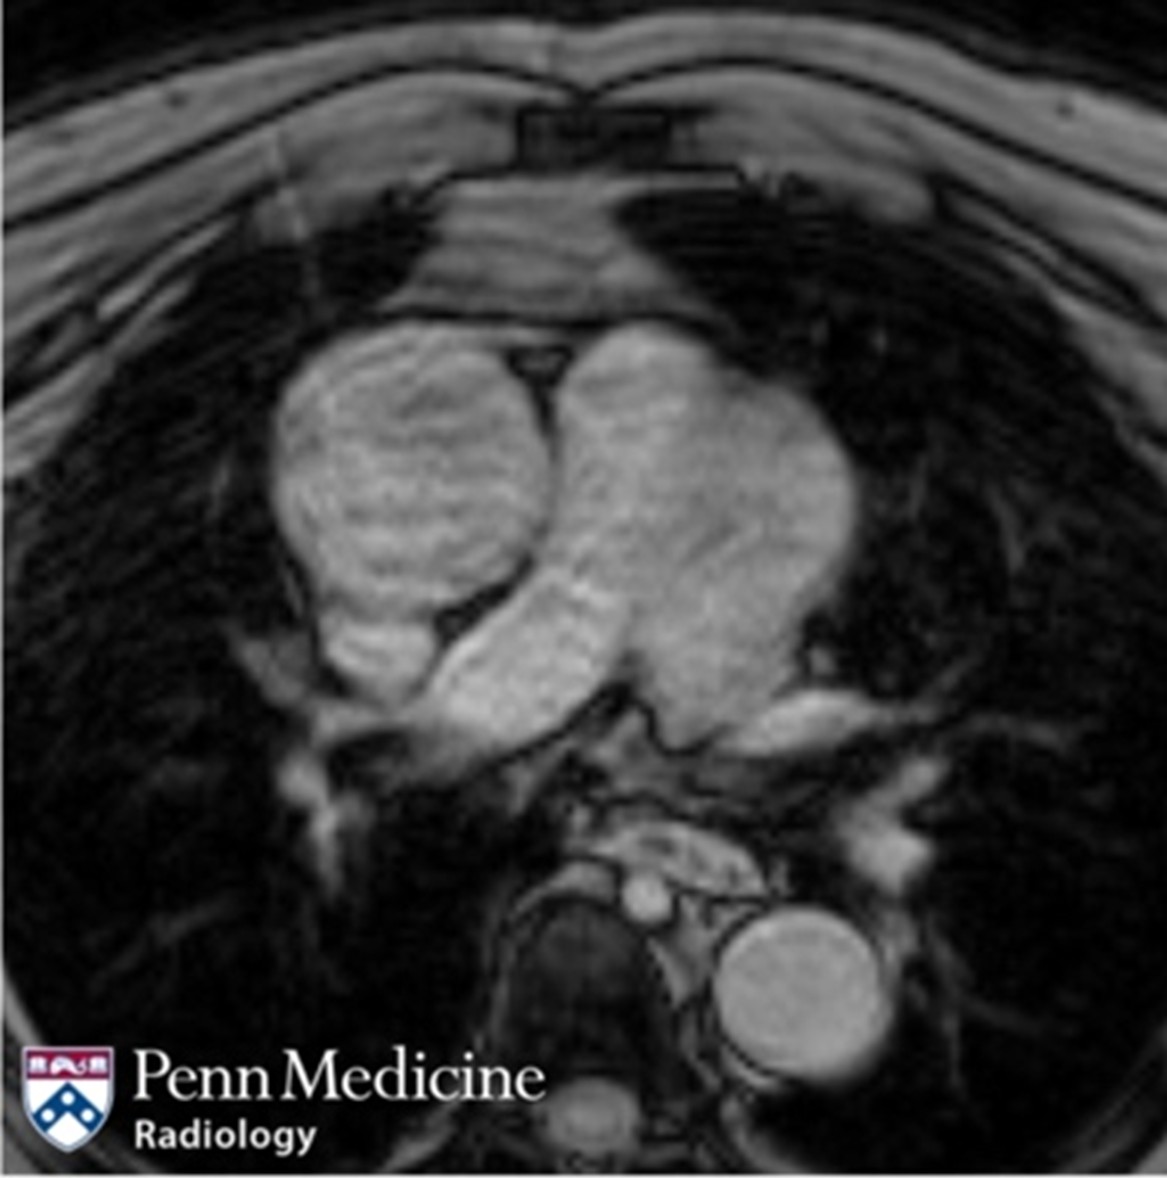

70-year-old man with left-sided chest pain

A 70-year-old man presented with concern of left-sided chest pain.